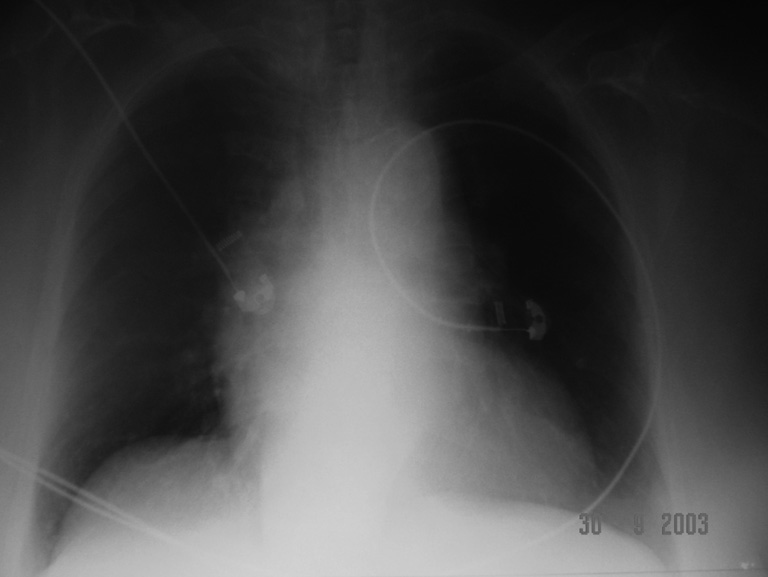

Cas clinique : Figure 2